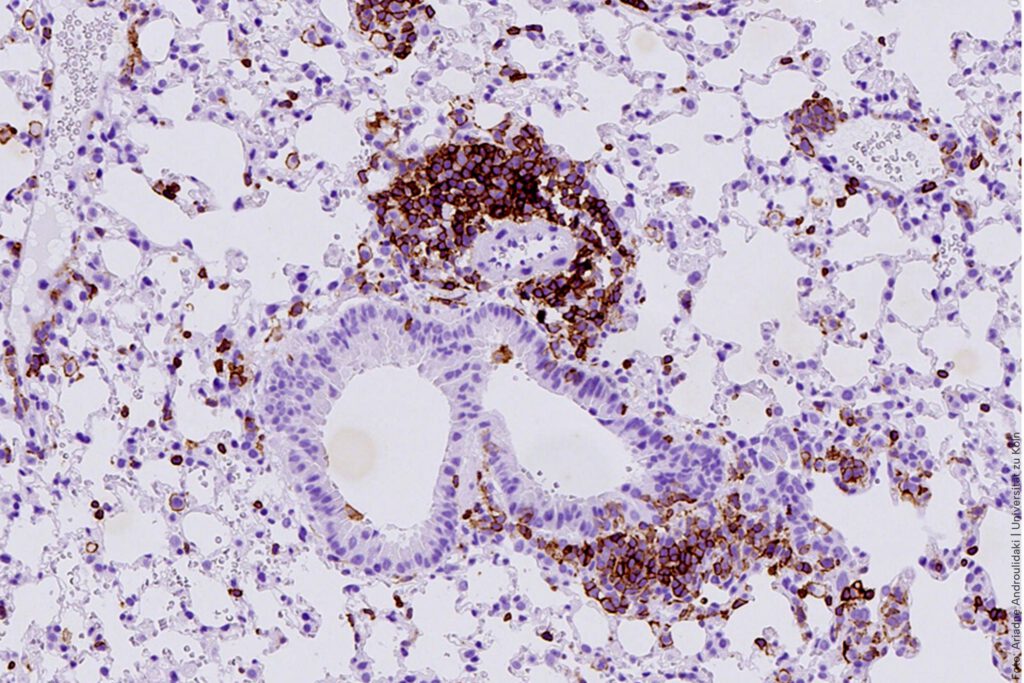

Im Lungengewebe dieses neuen Mausmodells zum kleinzelligen Lungenkrebs zeigt die CD45-Färbung eine frühe Entzündung, die bereits vor der Tumorbildung auftritt. Die braun markierten Bereiche kennzeichnen Immunzellen, die sich im Gewebe anreichern. © Ariadne Androulidaki

Bild: © Ariadne Androulidaki